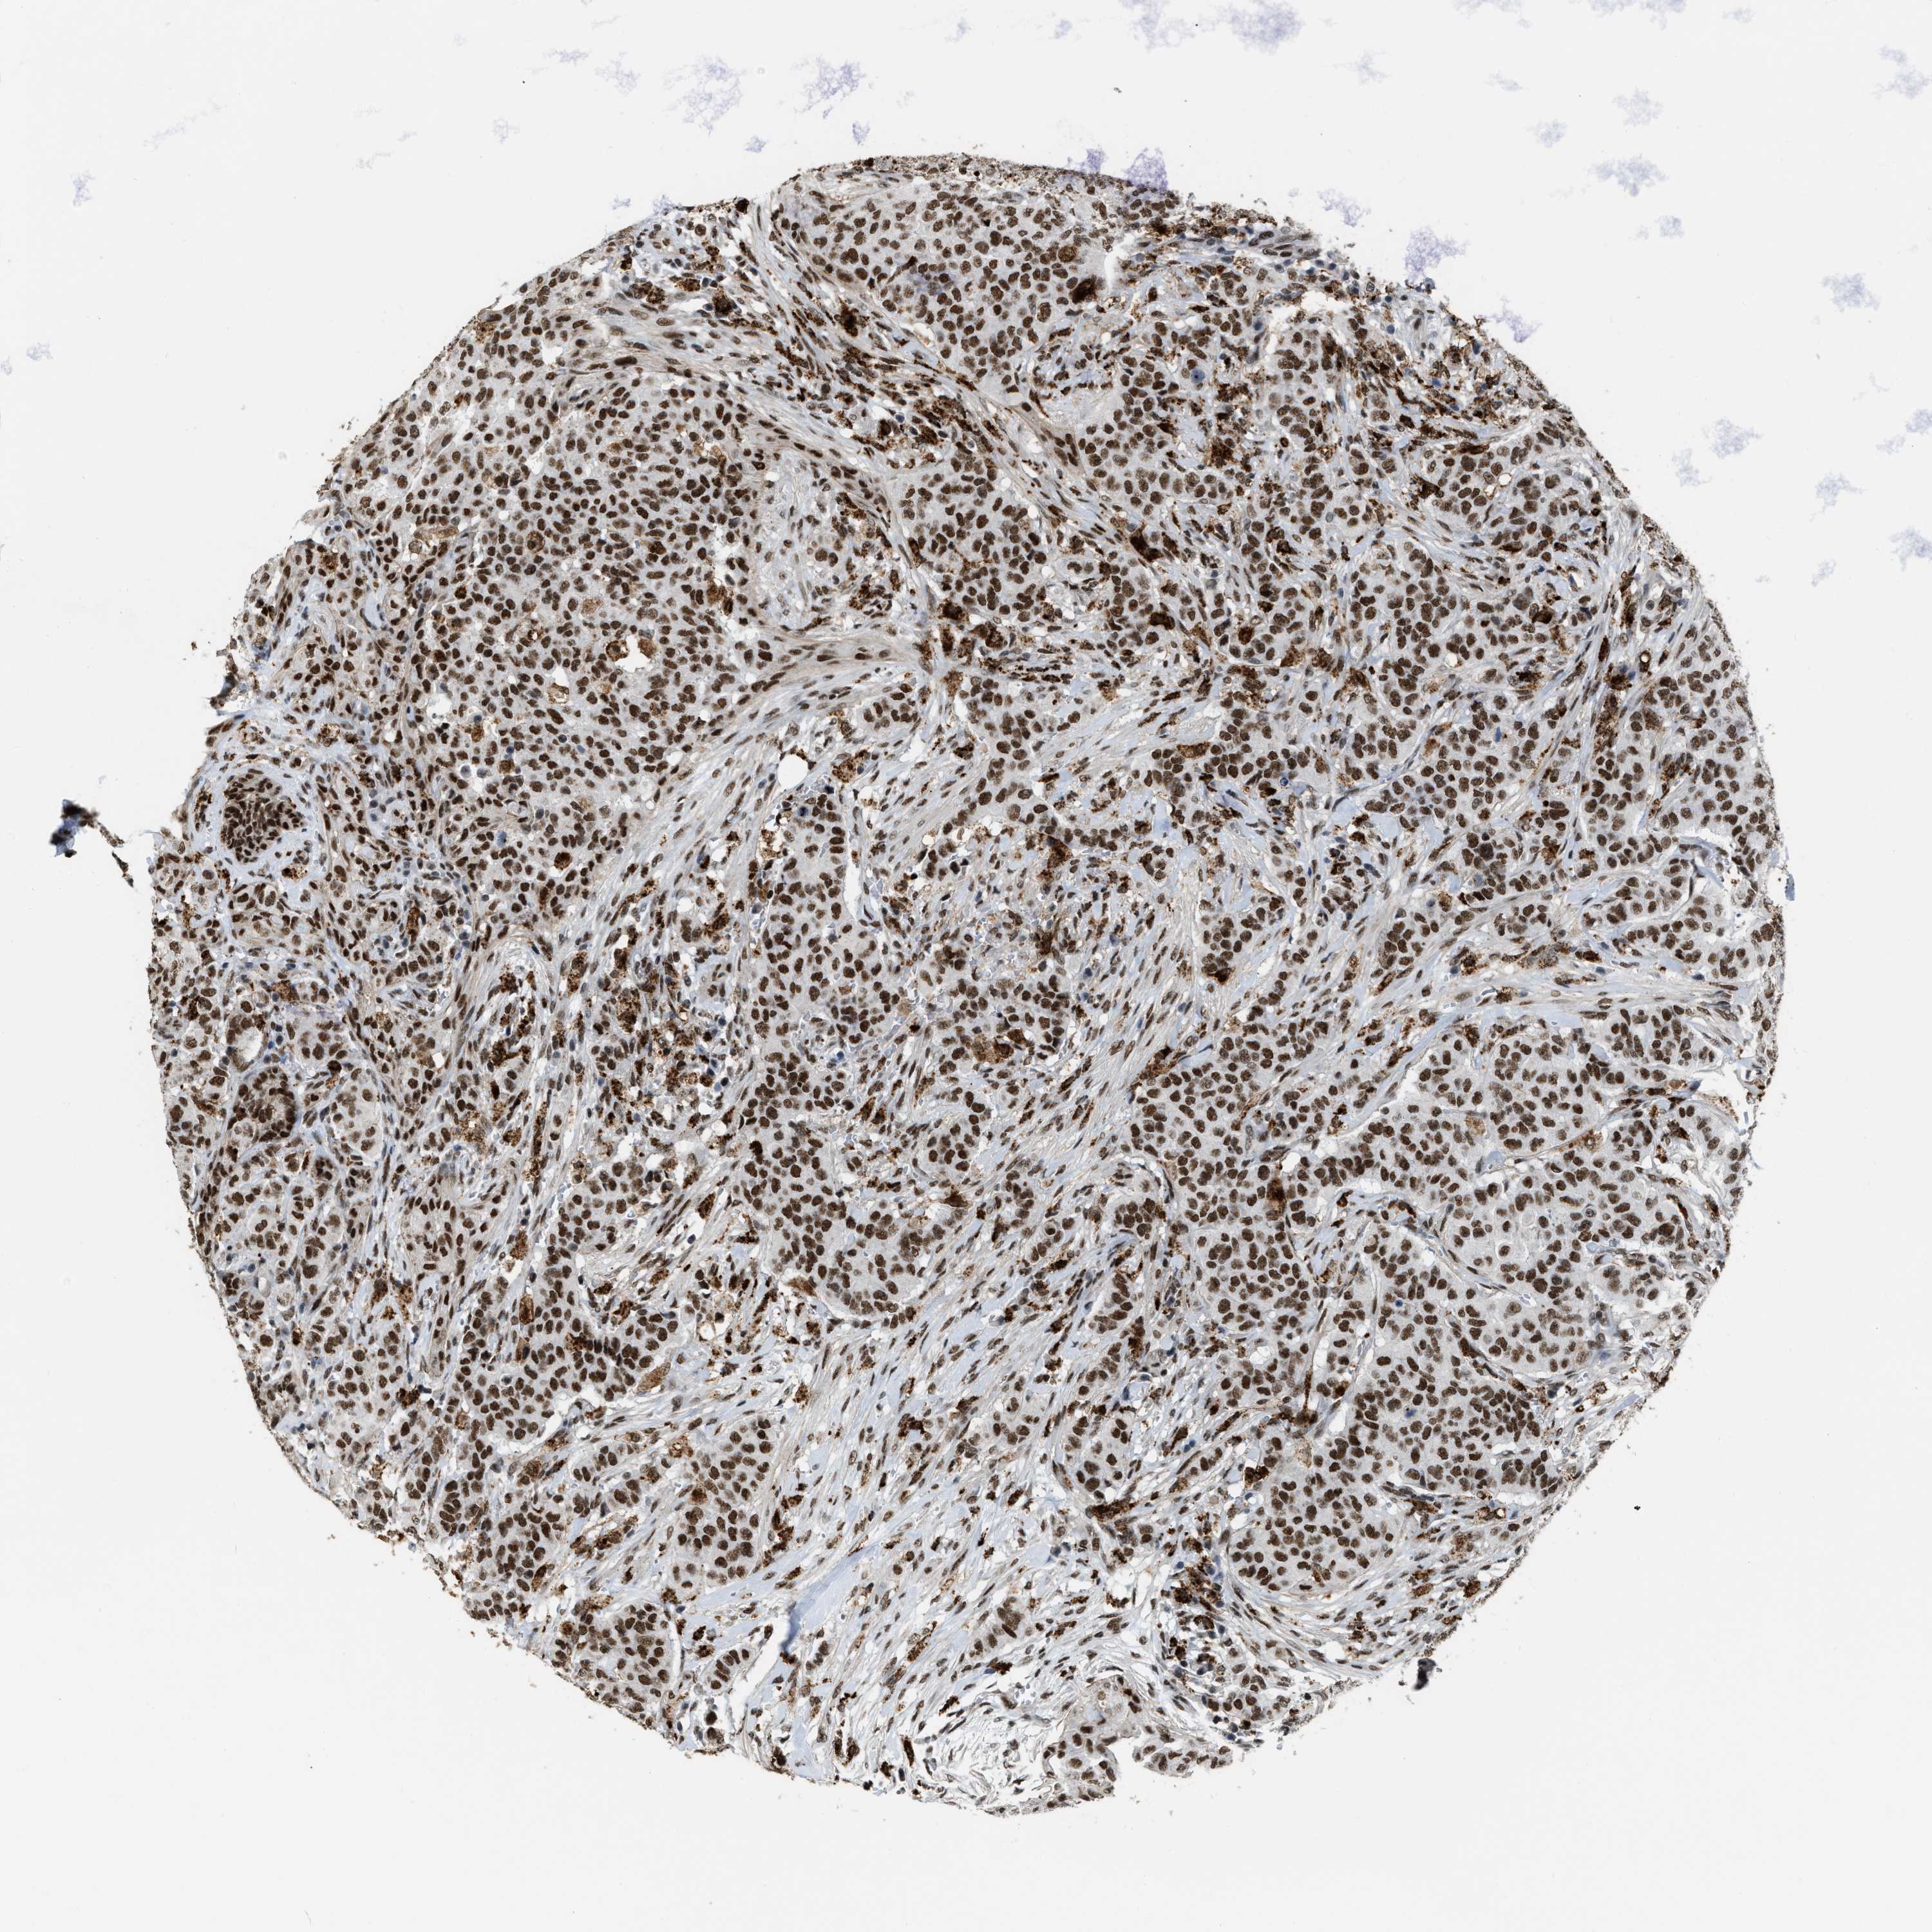

CANCER BREAST CANCER Show tissue menu

BRCA TCGA BRCA VALIDATION PROTEIN EXPRESSION